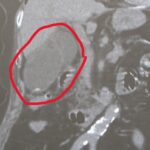

総合病院に通院している90代の方

2026年4月15日

総合診療医

普段高血圧で総合病院に通院している90代の元気な方です。 あしのむくみが気になり、ご家族と受診されました。 CTで膵臓に腫瘍を認めます 普段、総合病院、大学病院に通院しているのに 気になることをお話されない方がとても多いと感じています。 それは、患者さんが悪いわけでなく 医師が、患者さんが気になることを聞き出さないからです。 医師と患者さんの関係が いつもの薬 だけでつながっているだけでは 気軽...